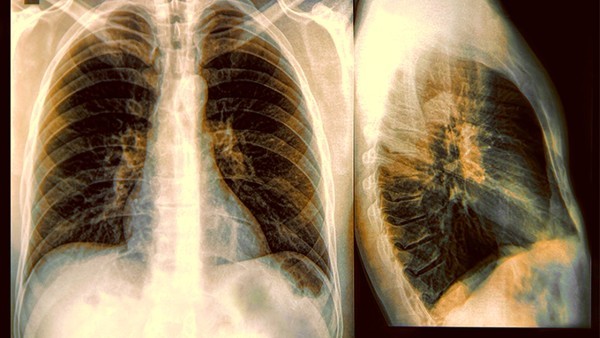

局部激素类药物是过敏性哮喘病人的首选药物,主要采用的就是喷雾剂以及口腔吸入的激素类药物。其中最好的应用方式就是口腔吸入法,因为这样能够将药物当中的有效成分迅速送达到人体的肺部当中,同时还能够大大降低药物给人体所带来的不良反应。较为常见的药物主要为舒利迭以及信必可都等。一般需要根据病人的肺功能以及具体的症状表现来给予相关的用量。同时这种药物需要长期使用才能够见效。